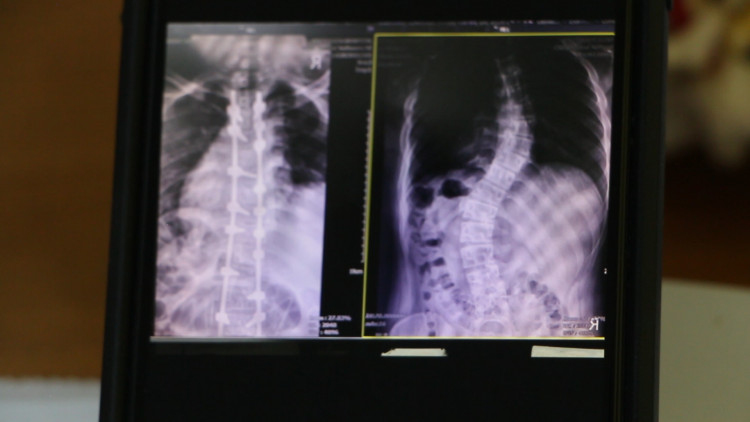

นพ.พงศธร กล่าวอีกว่า กรณีของน้องโทนี่ เด็กหญิงวัย 14 ปี ชาวอำเภอชุมแพ ที่ผู้ปกครองเชื่อว่าอาการหลังคดน่าจะมาจากการสะพายกระเป๋านักเรียนที่มีน้ำหนักมากนั้น ก็อาจจะเป็นไปได้ แต่ก็อาจจะไม่ใช่สาเหตุหลัก เพื่อความแน่ชัดจึงต้องทำการตรวจอย่างละเอียดอีกครั้ง ซึ่งแนวทางการรักษาจากการดูแผ่นเอ็กซเรย์แล้วถือว่าอยู่ในระดับปานกลาง สามารถรักษาโดยการสวมใส่เครื่องดามกระดูสันหลังเอาไว้ แต่ในกรณีที่เป็นในระดับรุนแรงก็จะต้องทำการรักษาด้วยวิธีการผ่าตัดเพื่อจัดกระดูกให้เข้าที่ ซึ่งวิธีการรักษานี้ผู้ที่มีอาการจะต้องได้รับการบำบัดฟื้นฟู จึงขอฝากไปถึงผู้ปกครอง โดยเฉพาะผู้ที่มีบุตรหลานเพศหญิงให้หมั่นสังเกตว่า บุตรหลานมีรูปร่างผิดปกติหรือไม่ เช่น ไหล่ทั้ง 2 ข้างเท่ากันหรือไม่ กระดูกสันหลังคดเอียงแค่ไหน รวมทั้งสะบักเท่ากันทั้ง 2 ข้างหรือไม่